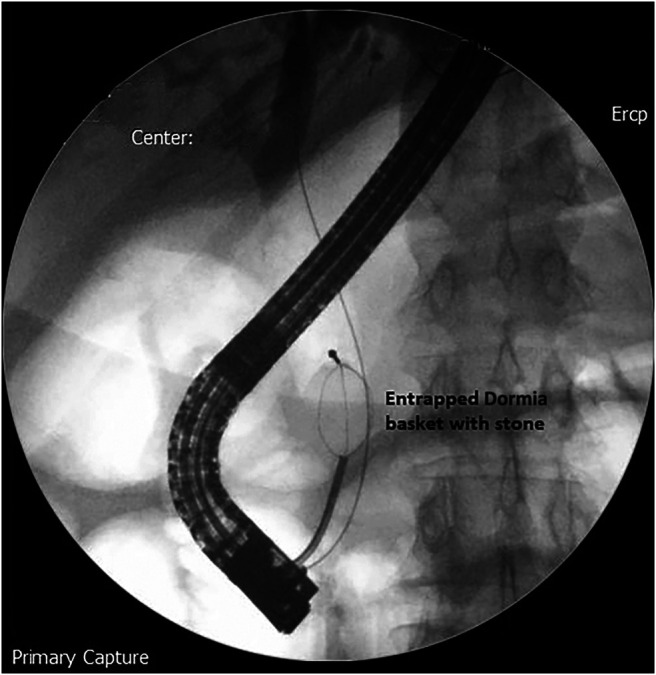

The stone was grasped with the Dormia basket, and multiple attempts to crush and retrieve it remained unsuccessful, resulting in the entrapment of the Dormia basket with the impacted stone (Figure 2). Balloon sphincteroplasty to 16 mm was performed for extraction of the entrapped basket and stone with no success (Figure 3). Subsequently, it was decided to use a novel technique of cholangioscope-guided EHL to dislodge and retrieve the entrapped basket. Basket wires were cut from the proximal end to release tension for the facilitation of retrieval. A single-operator intraductal cholangioscope was advanced with direct visualization of the stone and entrapped basket. EHL was performed for stone fragmentation (Figure 4). After fragmentation, a wire-guided extraction balloon was placed within the entrapped basket and fragmented stones. The extraction balloon was then inflated to 15 mm, which released the entrapped wires, and subsequently, the basket was retrieved successfully (Figure 5). Stone fragments were retrieved with the extraction balloon, and an occlusion cholangiogram confirmed clear ducts (Figure 6). The patient was discharged on the same day with no procedure-related complications.